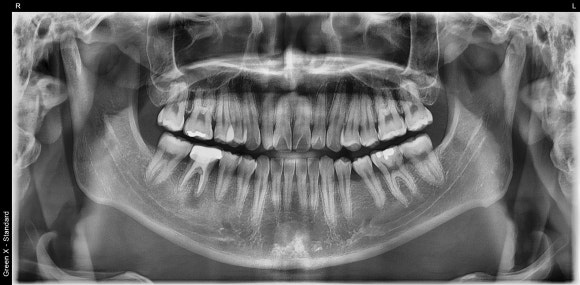

20241224

이때 CT는 아주 고마운 진단도구입니다.

이전 치료에서 놓친 것은 무엇인지,

염증의 정확한 위치와 크기는 어느정도인지

사전에 파악할 수 있게 도와줍니다.

따라서

재신경치료의 가능성 여부를

어느 정도 가늠할 수 있는 근거가 됩니다.